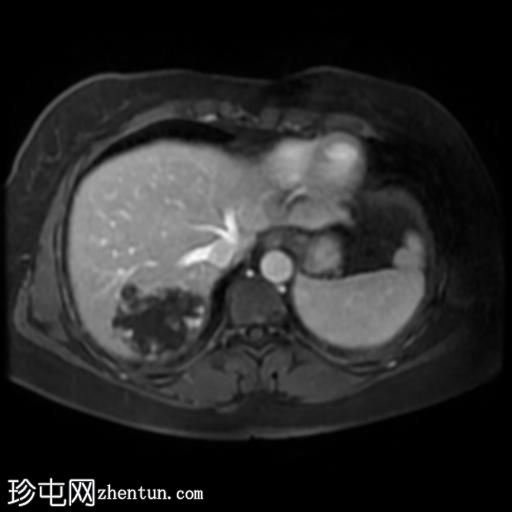

轴位T1加权像增强扫描

脂肪抑制动态增强扫描

肝脏第7段可见一边界清晰的分叶状肿块。T1加权像呈低信号,T2/T2脂肪抑制序列呈高信号,动脉期呈不连续结节状周边强化,门静脉期呈向心性强化,延迟期完全强化。DWI序列呈高信号,ADC值呈混合信号。